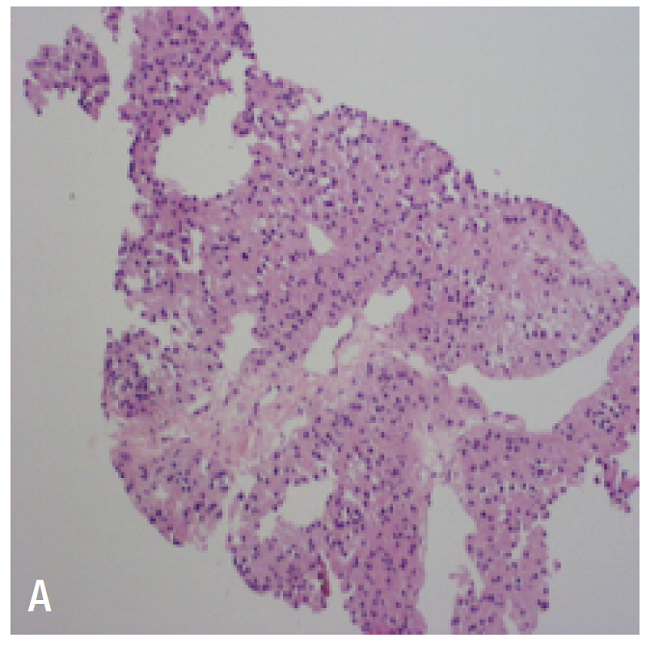

A biopsy was performed on one of the liver lesions, revealing findings compatible with adrenal cortex tumor and extensive necrosis. Calretinin, melan-A and cytokeratin AE1-AE3markers were positive, with negative CD117 and chromogranin (Figure 3).

To histologically differentiate adenoma from cortical carcinoma, the World Health Organization adopted the Weiss score. With it, malignancy is diagnosed when at least three criteria are met, including high nuclear grade, high mitotic rate (>5 mitoses per 50 high-power fields), atypical mitotic figures, less than 35% clear cells, altered architecture, tumor necrosis, venous invasion, sinusoidal invasion, and capsular invasion. 3 The positive immunohistochemical markers in ACC are steroidogenic factor 1, inhibin alpha, melan-A and calretinin. 3